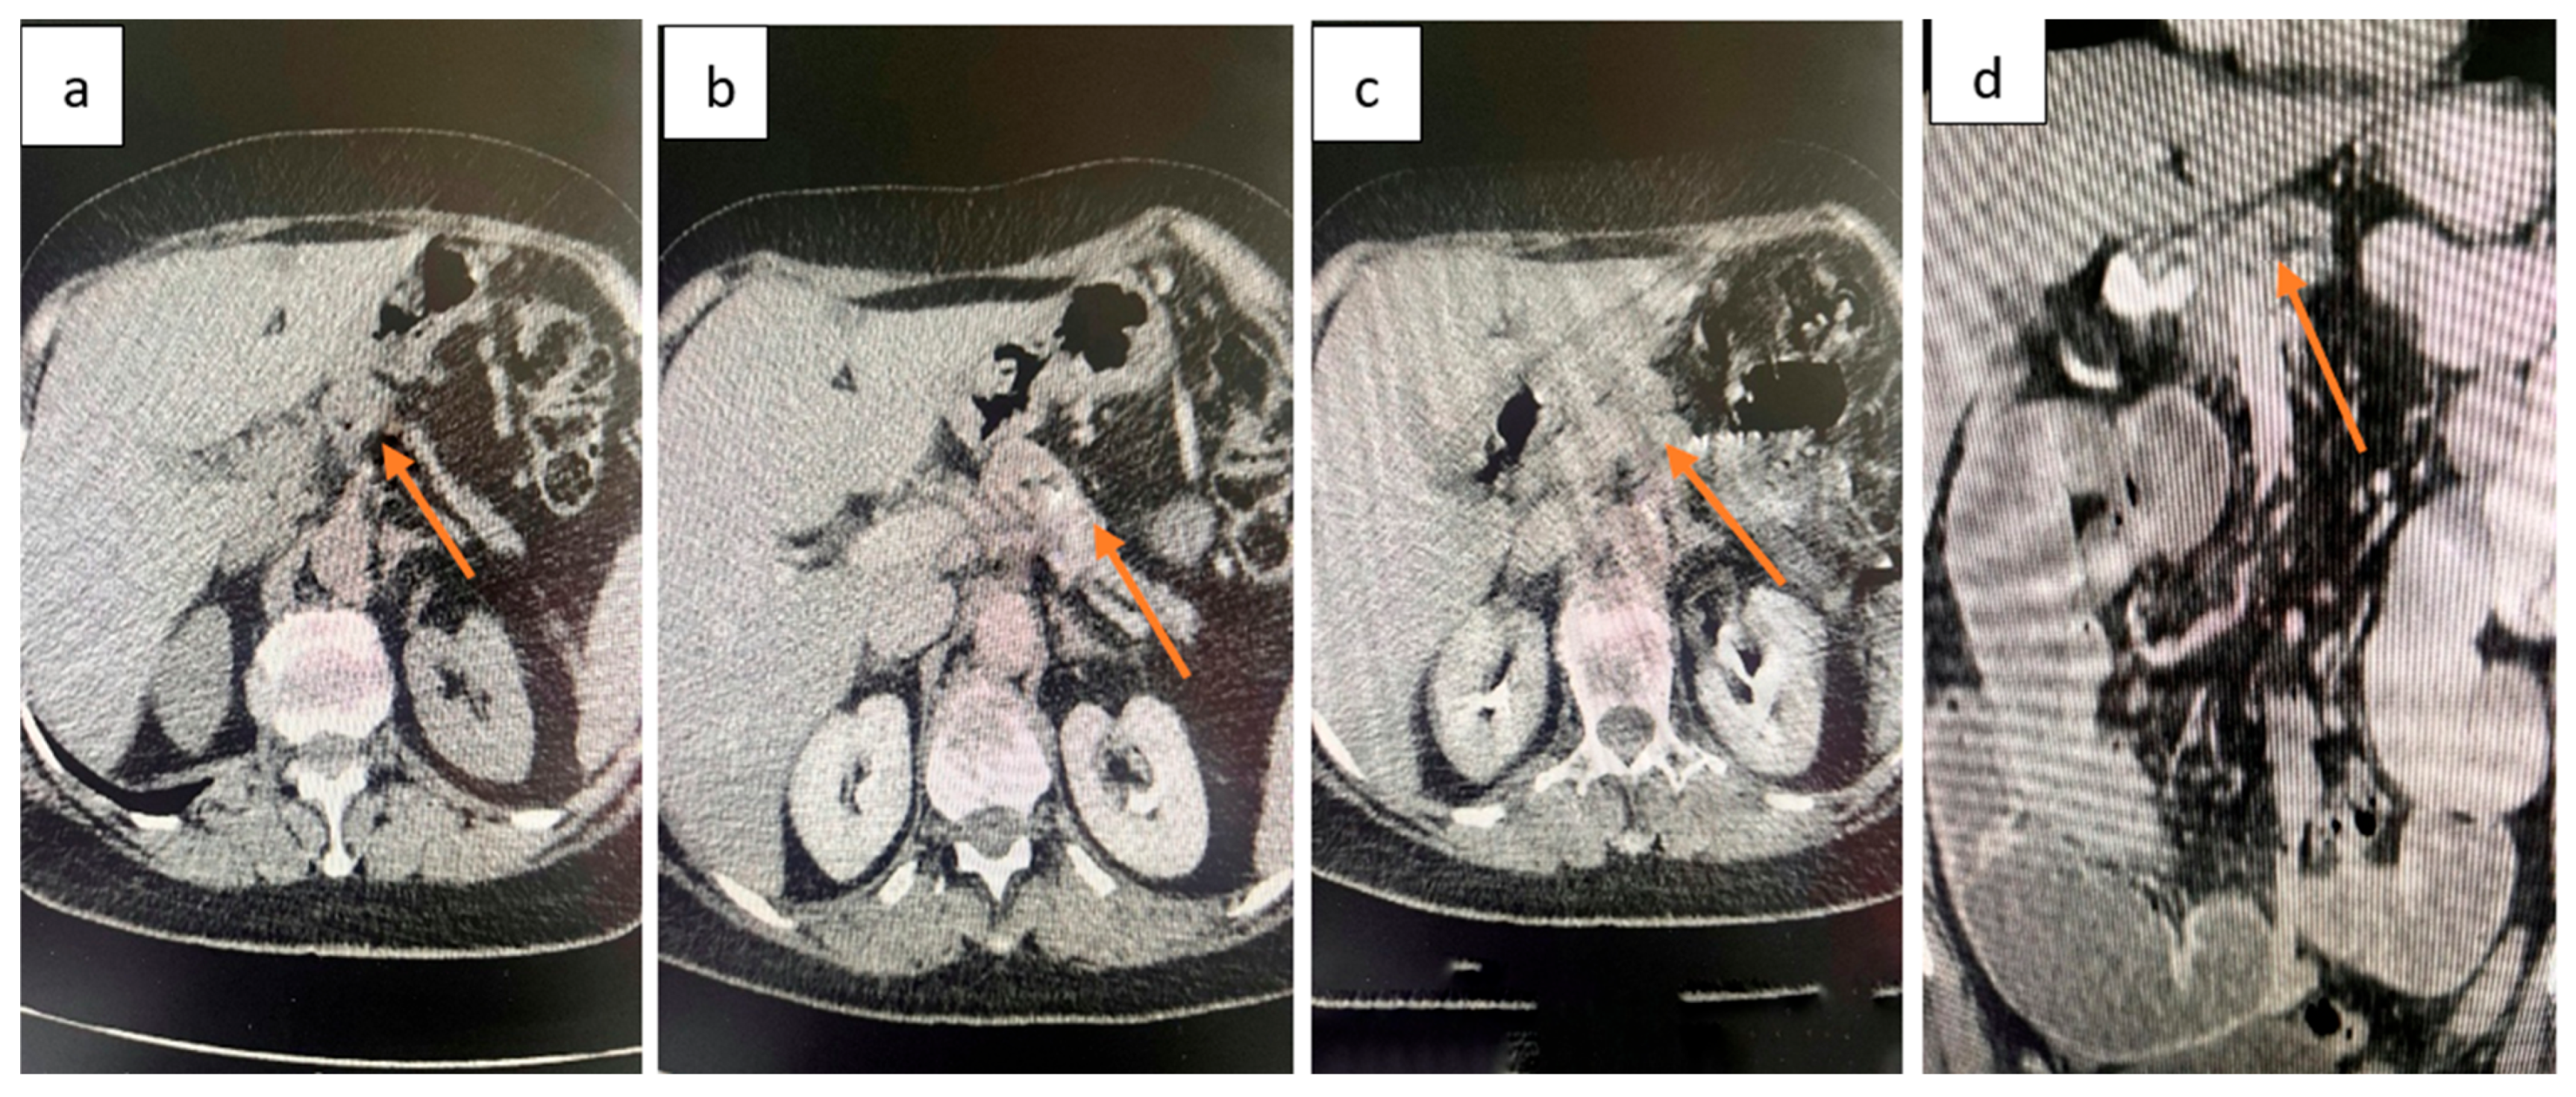

2.4. Diagnostic Assessment

2.5. Therapeutic Intervention